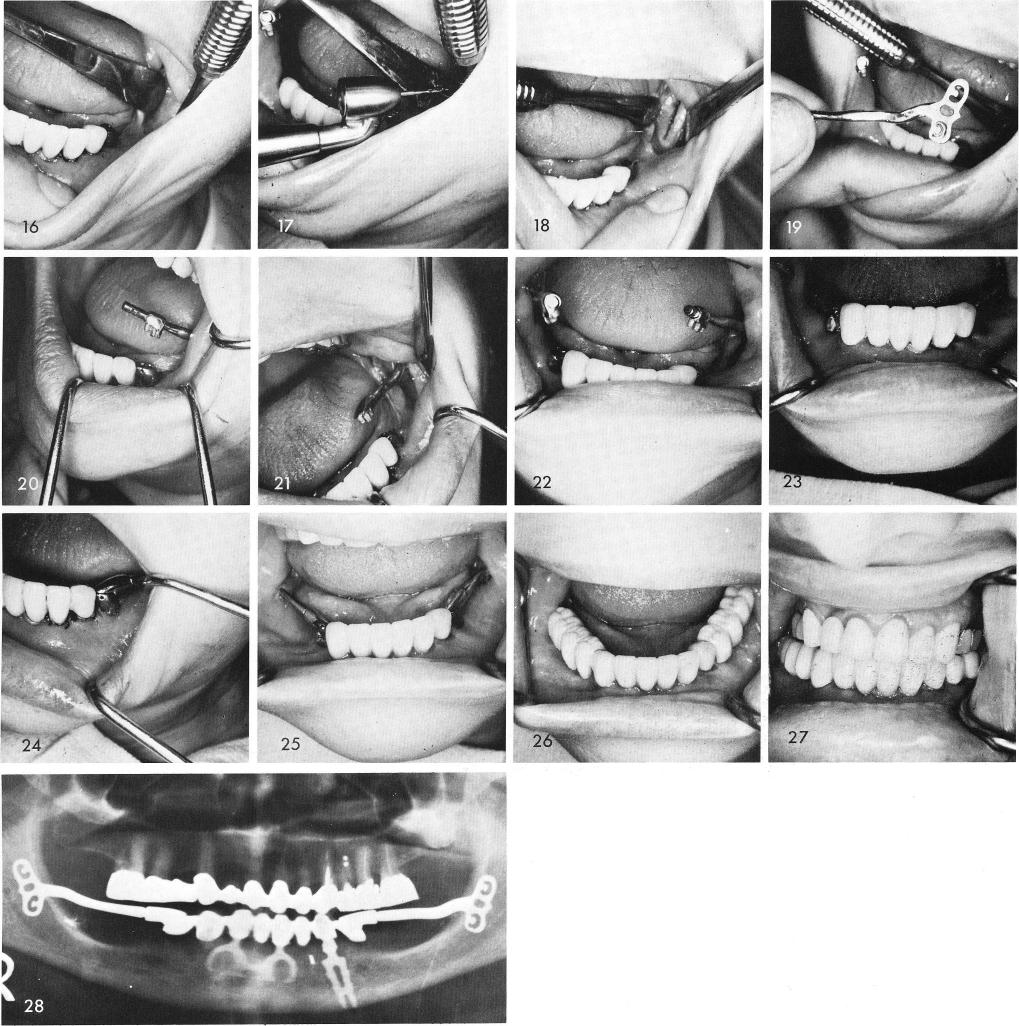

The ramus is exposed and a groove is made on the buccal side, figs. 11, 12, and the blade with its anterior cable is tapped into place so that the cable was tipping upward from the occlusal plane, fig. 13. The hollow tube with its male figure eight lock is fitted to the cable, figs. 14, 15. Steps are repeated on the opposite side, figs. 16, 17, 18, 19, 20, 21, 22. The tubes with the cables are adjusted mesially and distally as they are tapped downward to engage the female locks and then cemented into position, figs. 23, 24. One week later the tissues are healed, fig. 25, and the posterior restorations were cemented over the cables, figs. 26, 27. Fig. 28 shows the post-operative x-ray.